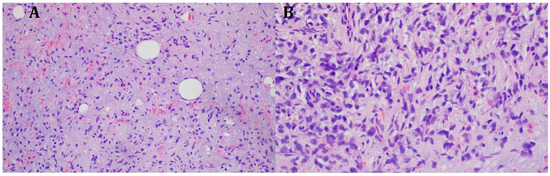

On the 11th day of the puerperium, the patient presented at the gynecology ward again during overnight hours due to the sudden appearance of a tumor in the medial part of the right thigh. The lesion was non-painful, mobile, soft, approximately 20 cm in diameter, and protruded above the level of the rest of the thigh surface. It was not accompanied by visible skin lesions. Owing to the sudden onset and clinical presentation of the lesion, a preliminary diagnosis of soft-tissue hematoma during the rupture of a venous vessel was made. An ultrasound examination (GE Voluson S10 Expert; BT16, 2019; convex 3/4D RAB6-RS transducer; General Electric Company, Schenectady, USA) showed an oval, focal, and confined space of variable echogenicity, measuring 15.74 × 8.59 cm, with a superficial localization involving the soft tissues of the right thigh and the lower pole reaching the quadriceps muscle (Figure 1).

Figure 1.

Ultrasound image of right thigh tumor (GE Voluson S10 Expert; BT16, 2019; 3/4D convex probe RAB6-RS) Red circle- tumor.